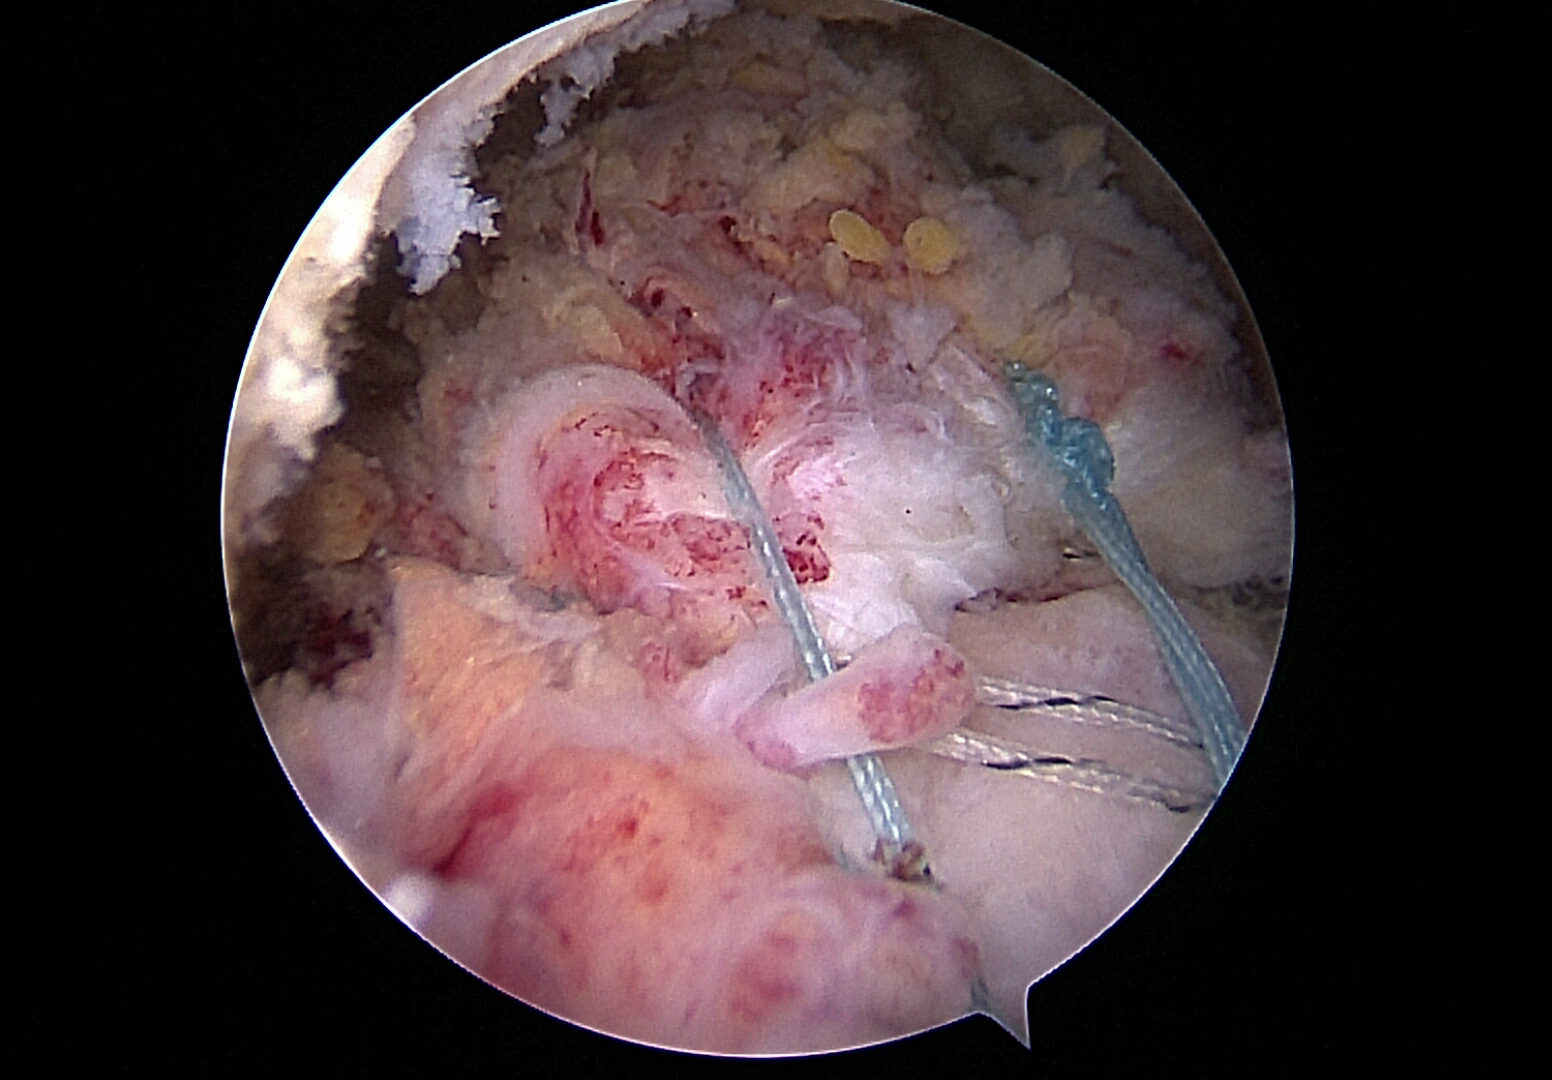

Reconstructed rotator cuff

Arthroscopic (arthroscopy) e-reconstruction is a minimally invasive procedure in which the torn tendons are precisely reattached to the bone using small incisions and a camera (arthroscopy).

This method offers numerous advantages: less tissue damage, shorter healing time, less pain after the operation and faster rehabilitation overall.